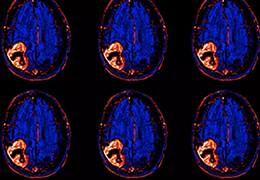

ART-Plan™ Artificial Intelligence Contouring